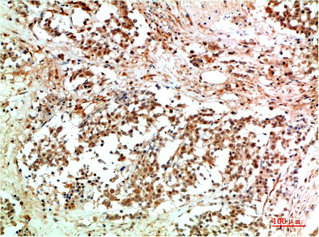

• Immunohistochemical analysis of paraffin-embedded Human Breast Carcinoma Tissue using JAK2 Rabbit pAb diluted at 1:200